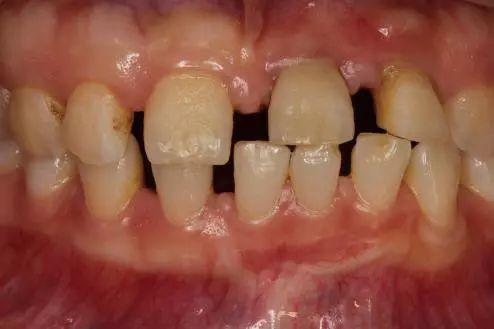

▍ 异常3:异位萌出

孩子牙齿不齐,要等换牙后再矫治吗?#雅悦齿科#

第三种情况是牙齿在不属于自己的位置萌出,我们叫做异位萌出。这种情况,医生需要评估该牙齿的位置对相邻牙齿、牙列还有牙槽骨发育有没有影响,如果有影响就需要及时干预。